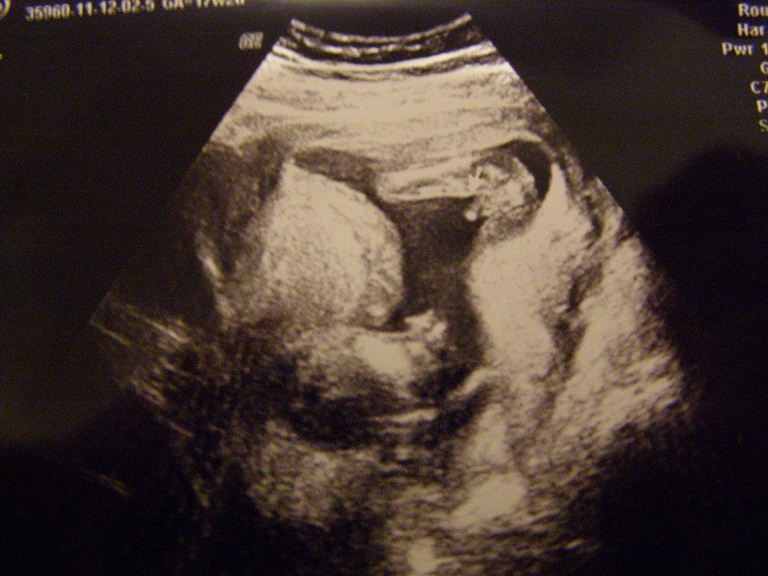

Zdjęcie z 2.12.2011

12tydzień- nie dało się ukryć ,że będzie chłopiec:)